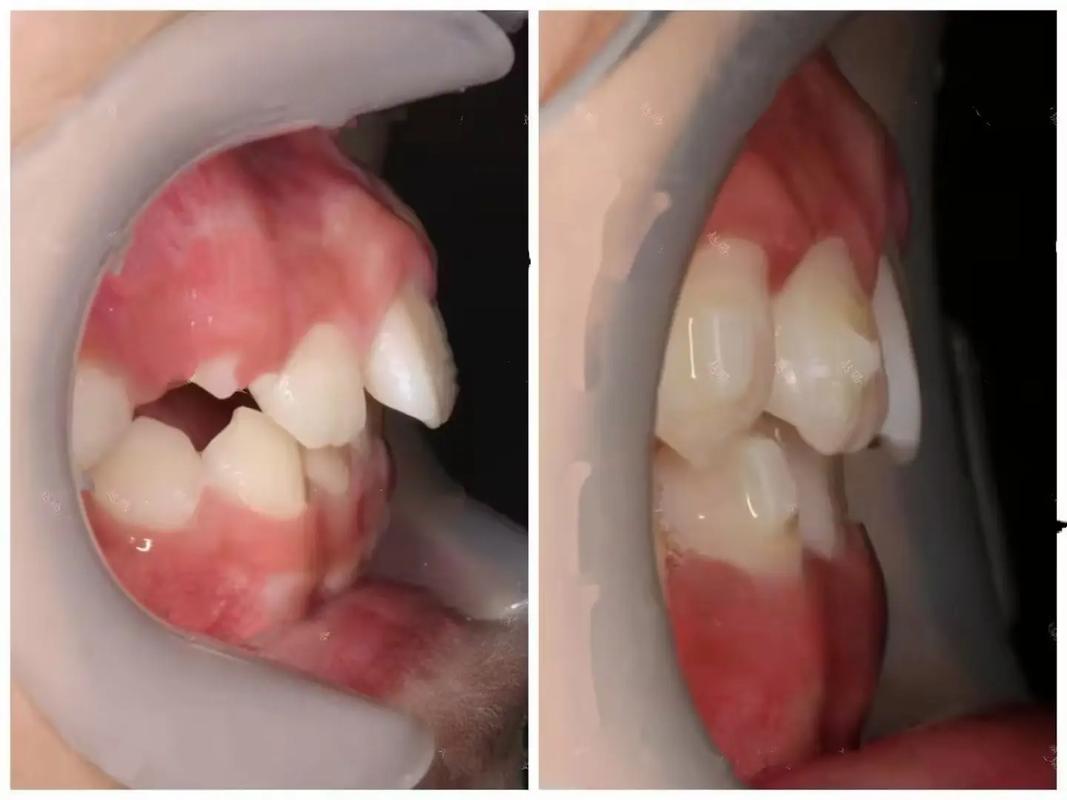

前排牙齿不齐是口腔中常见的牙齿排列问题,主要表现为门牙拥挤、错位、缝隙过大或扭转倾斜等,不仅影响面部美观,还可能对口腔功能、咀嚼效率及心理健康造成潜在影响,随着口腔医学技术的进步,通过科学的牙齿矫正可以有效改善这一问题,恢复牙齿的整齐度和咬合功能。

前排牙齿不齐的多重影响

前排牙齿位于口腔前部,其整齐度直接影响口腔功能、健康及心理状态,具体表现为:

美观与心理影响

前排牙齿不齐(如“龅牙”“地包天”“牙齿拥挤”)会破坏面部对称性和笑容美观性,部分患者因此产生自卑心理,不敢大笑、社交,甚至影响心理健康。